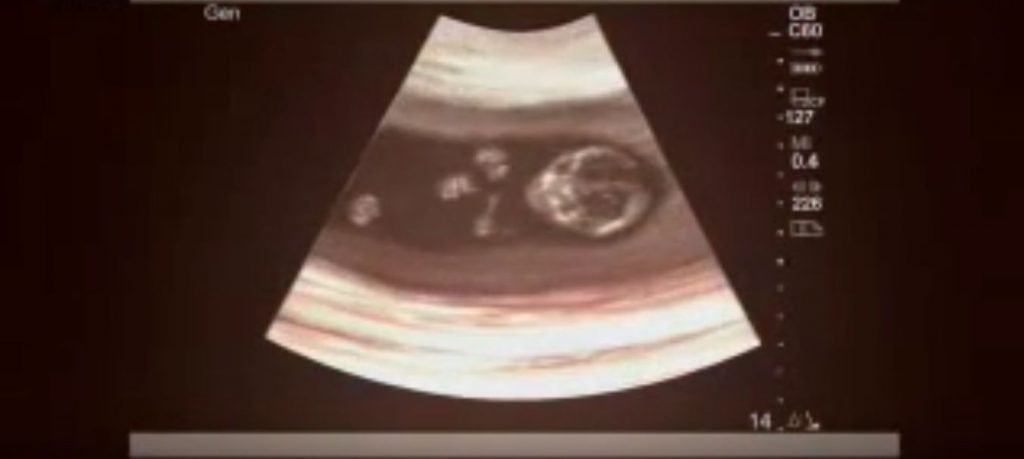

Claire face parte dintr-o categorie extrem de rara de bebelusi care au supravietuit avortului. Iar ca povestea sa fie si mai surprinzatoare, trebuie mentionat faptul ca ea a avut o sora geamana, care din pacate nu a supravietuit avortului.

„Esti inca insarcinata. Avortul a fost facut cu succes insa esti inca insarcinata. Erai insarcinata cu gemeni. Inca ai un bebe in burtica” i-a spus medicul.

La doar doua saptamani dupa ce mama sa a aflat aceasta veste, Claire a venit pe lume.

Cantarind putin peste 1500 de grame, Claire s-a nascut cu talipes equinovarus (o malformatie congenitala a picioarelor) si cu ambele solduri dislocate si a ramas in spital conectata la aparate mai bine de 2 luni.